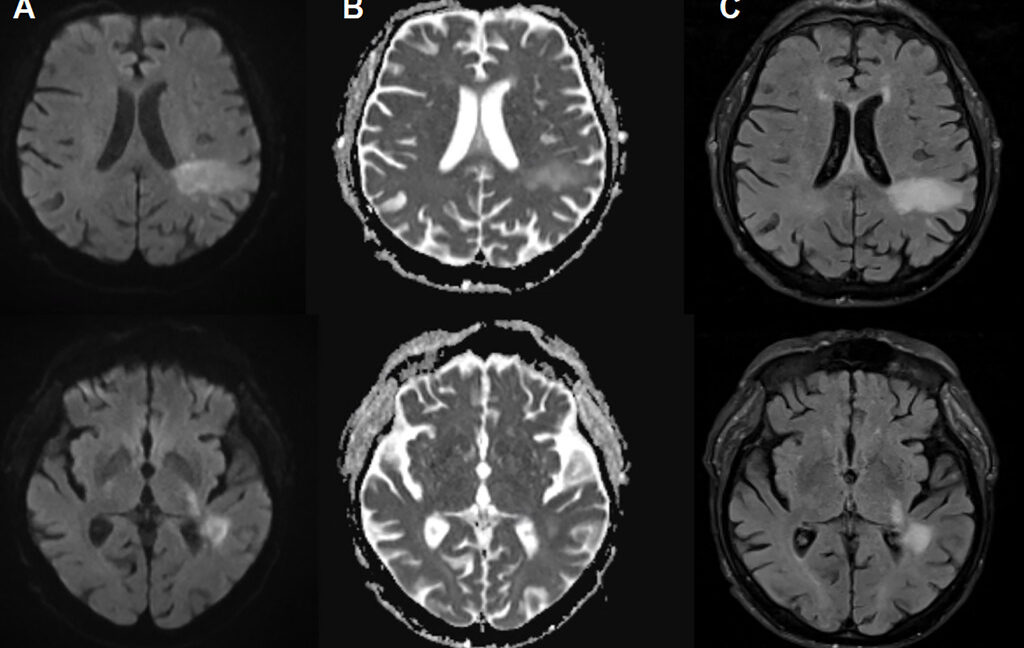

МРТ очагов прогрессирующей мультифокальной лейкоэнцефалопатии (ПМЛ) у пациента с хроническим заболеванием почек. Источник : Annals of Internal Medicine: Clinical Cases, 2026 .Текст рассказа Размер Маленький Стандартный Большой Ширина * Стандартный Широкий Ссылки Стандартный Оранжевый * Только для подписчиков

При прогрессирующей мультифокальной лейкоэнцефалопатии (ПМЛ) новый вирус, вызывающий заболевание, или «ПМЛ-тип» вирус JC, активно проникает в мозг, разрушая определенные клетки мозга, включая клетки, образующие изолирующие миелиновые оболочки, защищающие нервные клетки. Это приводит к обширной демиелинизации, что вызывает дисфункцию и гибель нервных клеток. На снимках ПМЛ может проявляться в виде характерных очагов поражения в головном мозге. Эти очаги, выявленные при визуализации, в сочетании с результатами анализа ДНК вируса JC в спинномозговой жидкости, являются основанием для диагностики ПМЛ. Однако у пациентов с ПМЛ симптомы могут имитировать все, от инсульта до рассеянного склероза, вызывая такие проблемы, как нарушения речи, дефекты зрения, двигательные нарушения и судороги.

Первоначально врачи предположили, что его неврологические проблемы вызваны уремической энцефалопатией — снижением функций головного мозга вследствие накопления токсинов при почечной недостаточности. Его лечили диализом, но трудности с подбором слов только усугубились. В этот момент провели нейровизуализацию, которая выявила поражения, характерные для прогрессирующей мультифокальной лейкоэнцефалопатии (ПМЛ). Вскоре анализ спинномозговой жидкости подтвердил наличие вируса JC в центральной нервной системе. Два дня спустя пациент скончался.